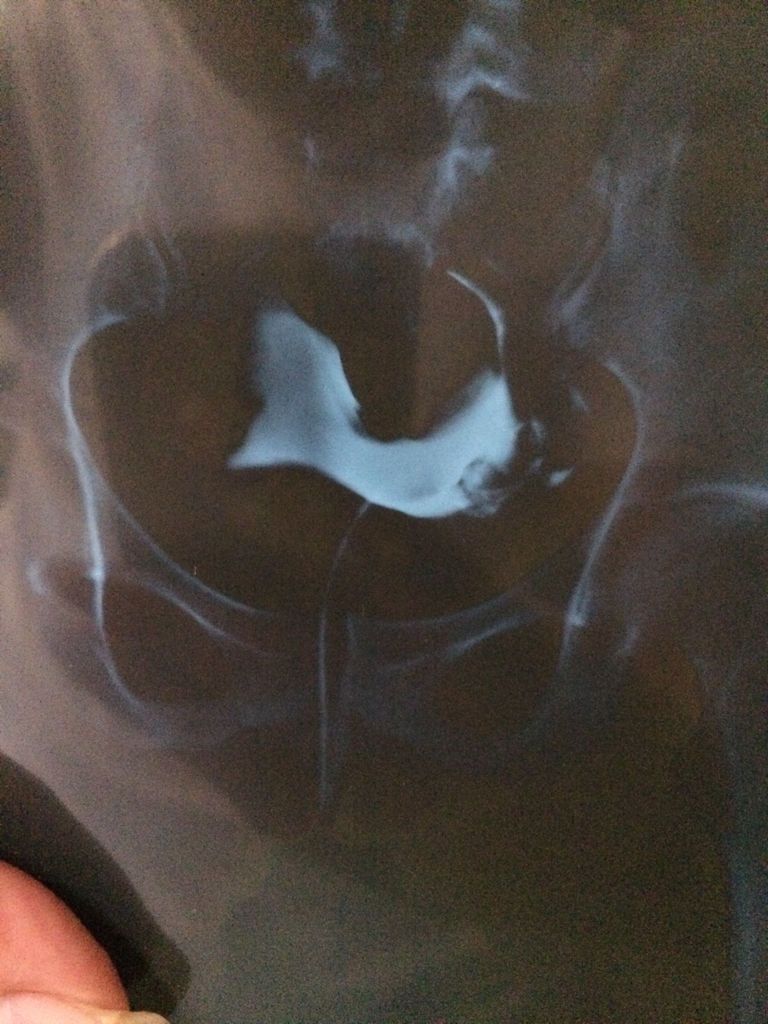

请快这张造影片上,是不是显示了输卵管双侧都堵塞了? 点击展开 母婴用户287280161 2016-09-01 10:35 满意回答 根据造影片子显示看貌夕没有发之蛇现明显的双侧输卵管,考虑双侧输卵管有堵挤殖狗塞的情况。 爱狂风一样舞蹈 2016-09-01 10:42 宝宝知道提示您:回答为网友贡献,仅供参考。 相关问题 帮忙看下输卵管造影片是什么问题,通吗? 输卵管造影片有效期多久 请专家帮忙看下我的输卵管造影片和文字报告 有造影片